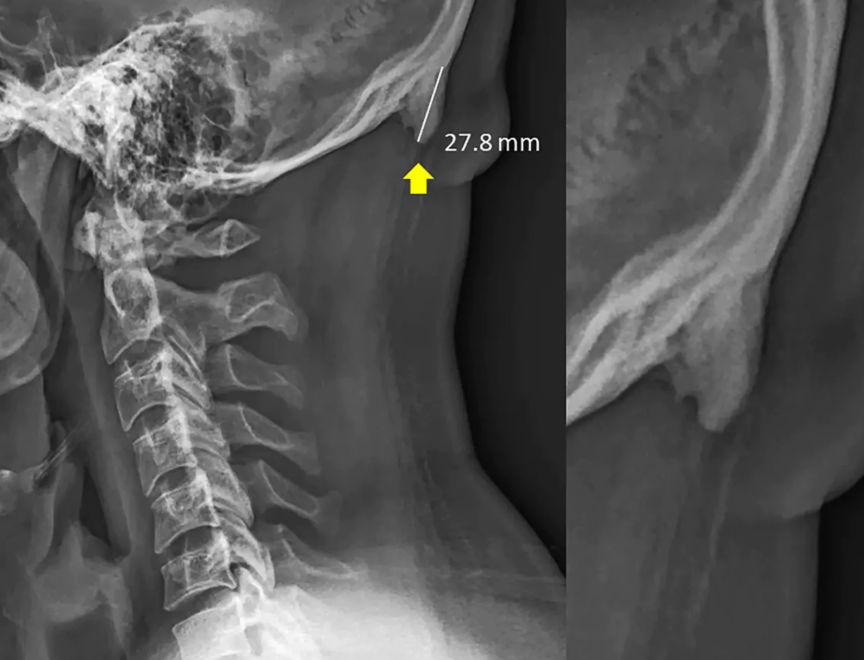

这个研究来自澳大利亚阳光海岸大学的一个医生,David Shahar。他在过去20年从医的经历中,发现越来越多的人,在后脑勺窝里、颈子上面的地方,出现了一个小小的凸起。这玩意儿,学名为“枕外隆凸”(external occipital protuberance)。他发现了这个现象之后,和同事一起“看了各个年龄的1200多张X光片”,发现在18-30岁的人中,这块小骨头出现的频率“异常高”。最大的一个枕外隆突案例,“角”甚至凸出来了接近3厘米。

然后,判定长出枕骨隆突(原 paper 根本没说“长角”,毕竟动物的角和骨骼的成分根本不同)的标准在10毫米,只要超过这个值,就在数据中算作是阳性,而不一定真的长“出来”了那个东西,文中配图里的案例其实非常极端。研究者把这些X光片按年龄和性别分了组,发现年轻人当中长出枕骨隆突的人要多一点点:35%的30岁以下的年轻男性有这个隆突,而在30-50岁的观察者中,此比例不到15%。